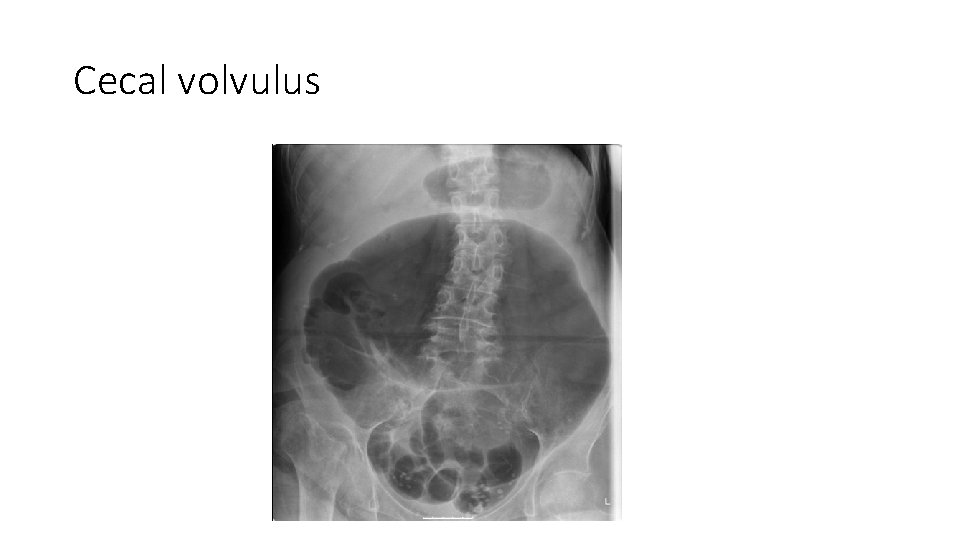

Plain radiographs • An upright chest radiograph is useful to screen for free air which would suggest perforation. • Flat and upright abdominal radiographs can help distinguish severe constipation from bowel obstruction. • Plain films may also help localize the site of obstruction (large vs small bowel). • Sigmoid or cecal volvulus may have a kidney-bean appearance on the abdominal films • Intramural air is an ominous sign that suggests colonic ischemia. • The absence of free air does not exclude perforation

Cecal volvulus